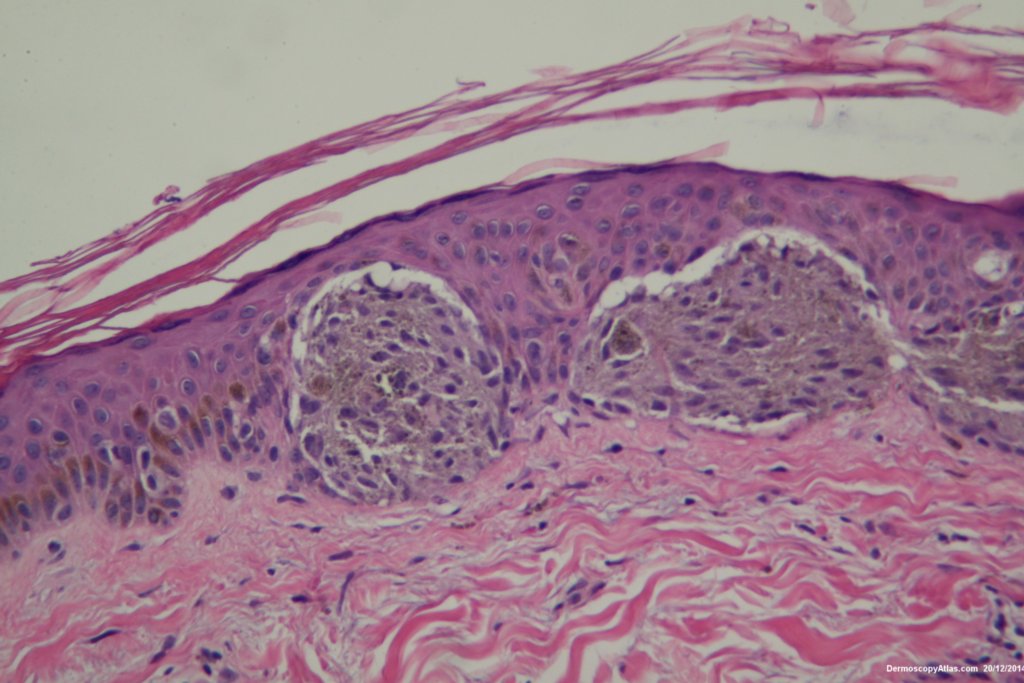

The dermatoscopy shows dark clods of varying sizes both peripheral and central. These represent nests of rapidly growing melanocytes. The lesion is dark because the nests press high into the epidermis giving a black colour. Sometimes cells are extruded into the stratum corneum exagerating the dark colour.

The histopathology shows nests of epitheliod and spindled cells with lots of melanin in them. There are a few melanophages in the dermis. There is no inflammatory reaction beneath this lesion. There were no mitoses. This is just a junctional lesion ie no nests of cells in the dermis.